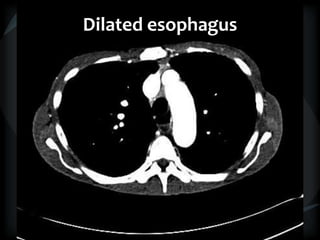

Dilated esophagus